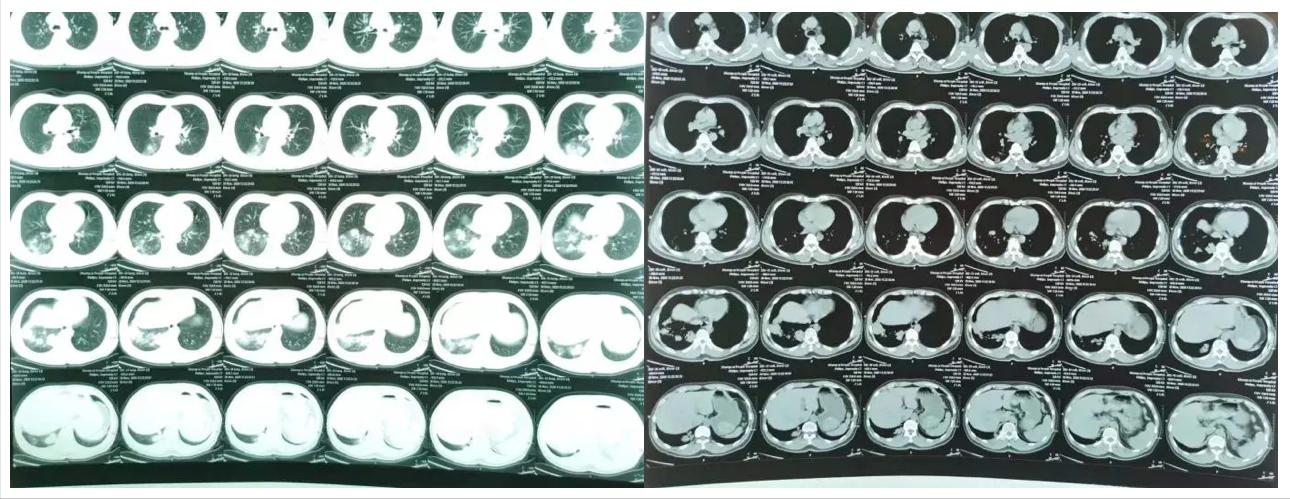

46岁的男性患者高某初次来我院治疗的时间是2020年12月20日。其主诉症状为 「咳嗽、胸闷10天,痰中带血12小时」 。据患者描述,入院10天前,自己无明显诱因即出现咳嗽,伴活动后胸闷,无发热、咳痰、胸痛、咯血症状,其先是到当地卫生院就诊,接受 「左氧氟沙星、哌拉西林钠、氨溴索」输液治疗5天 ,效果不佳。又到当地县级人民医院,行胸部CT检查(2020-11-30)示: 右肺下叶炎症 (图1),接受 「头孢哌酮舒巴坦」输液治疗3天 。入院12小时前,出现了 「痰中带血」 的症状, 色鲜红,量少,咳嗽、胸闷症状持续加重。

图1:胸部CT示右下肺炎症(当地县级人民医院)

抗感染治疗7天后,患者未再出现痰中带血,但咳嗽、胸闷症状无明显缓解。 复查胸部CT较院外旧片比进展 (图2)。

图2:胸部CT示右下肺炎症,可见空洞形成。